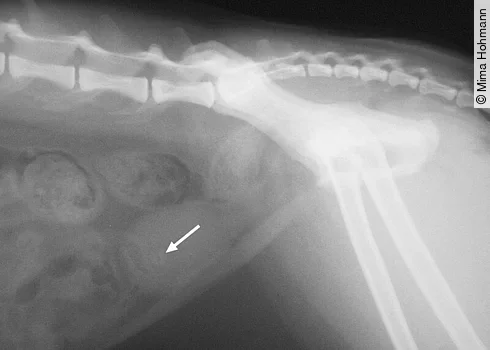

Bei der Palpation des Abdomens fallen bei der chronischen Obstipation die vermehrte Füllung der Darmschlingen und die harten Kotballen auf ([Abb. 5]).

Besteht die Obstipation längere Zeit, versucht die Katze durch Belecken des Abdomens wieder Bewegung in den Darm zu bekommen und die bestehenden Schmerzen zu „entfernen“, was ihr aber leider nicht gelingt. Fragen an den Besitzer, wie der Kot der Katze aussieht, wie die Konsistenz des Kotes beschaffen ist und wie oft die Katze Kot absetzt, helfen bei der Behandlung. Aus meiner Erfahrung kann ich sagen, dass oft ein „Leber-Feuer“ vorliegt.

Wie man sieht, sollte man eine Katze, die sich die Haare am Abdomen ableckt, auf alle Fälle röntgen. Der Vorteil des Röntgens: Man sieht nicht nur die Veränderungen an den Gelenken und der Wirbelsäule, sondern auch die Obstipation, Kristalle, Blasen-, Nieren- und Gallensteine, sondern auch Neoplasien, die ebenfalls ausstrahlende Schmerzen verursachen können.